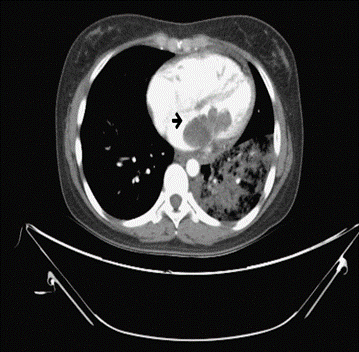

A 26-year-old female with no known medical history presented to our hospital for consultation regarding a cardiac mass found during a transthoracic echocardiogram. The patient complained of fever, bloody sputum for several days, progressive exertional dyspnea, and paroxysmal nocturnal dyspnea for a few months. The results of the laboratory tests were insignificant. Chest CT revealed a large isoechoic mass in the left atrium (Figure 1), as well as shown in transthoracic echocardiography with tricuspid regurgitation, pulmonary hypertension, and right heart systolic dysfunction. Under cardiopulmonary bypass and the guidance of transesophageal echocardiography, tumor excision, mitral annuloplasty, and tricuspid annuloplasty were performed (Figure 2). Histological examination revealed predominantly a hypocellular myxoid tumor, composed of spindle-to-round cells within a myxoid matrix (Figure 3). We observed a focal area of increased cellularity with mild to moderate nuclear pleomorphism. Mitotic activity was rarely identified. A focal myxoid degeneration and infarct-type necrosis were observed. The tumor was reminiscent of cardiac myxoma due to its predominantly myxoid matrix.

Figure 1: Post- contrast computed tomography: Revealing a lobulated low density in the left atrium, extending through mitral valve into left ventricle.